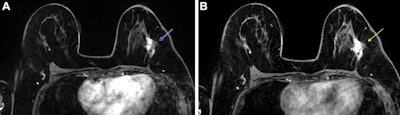

Post-neoadjuvant chemotherapy (NAC) MRI scans in a 66-year-old woman with invasive breast cancer show a lesion that appears fragmented in the first postcontrast axial T1-weighted image (arrow in A) but becomes more conspicuous and homogeneous in the last delayed phase (arrow in B). Despite these visual differences, response classification was identical between abbreviated and full diagnostic MRI. Pathologic analysis confirmed a partial response with residual invasive carcinoma.Post-neoadjuvant chemotherapy (NAC) MRI scans in a 66-year-old woman with invasive breast cancer show a lesion that appears fragmented in the first postcontrast axial T1-weighted image (arrow in A) but becomes more conspicuous and homogeneous in the last delayed phase (arrow in B). Despite these visual differences, response classification was identical between abbreviated and full diagnostic MRI. Pathologic analysis confirmed a partial response with residual invasive carcinoma.RSNA